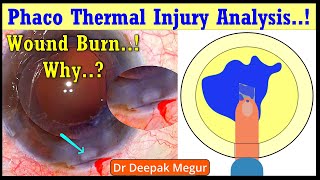

Wound burn due to hard brown cataract and its management Phaco thermal injury analysis..! Wound Burn , Why & How..? Dr Deepak Megur

Phaco thermal injury analysis..! Wound Burn , Why & How..? Dr Deepak Megur Secrets for post op clear cornea after Phacoemulsification of a rock Hard Cataract ..! Dr Deepak